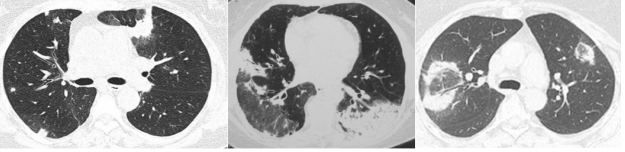

高分辨率CT(HRCT)是评估OP的重要检查手段,通常显示外周和多灶性实变,常伴有支气管充气征。此外,双肺可能存在斑片状实变、结节影、磨玻璃影、小叶周围浸润、支气管壁增厚和网状纤维化改变。磨玻璃影周围有实性密度的线状影形状如新月形或环状影称为“环礁征”。少数患者可见肺门和纵隔淋巴结增大,有时还可以观察到肺气肿或胸腔积液。

图片

图源:Front Med (Lausanne), 2023, 10:1146782.